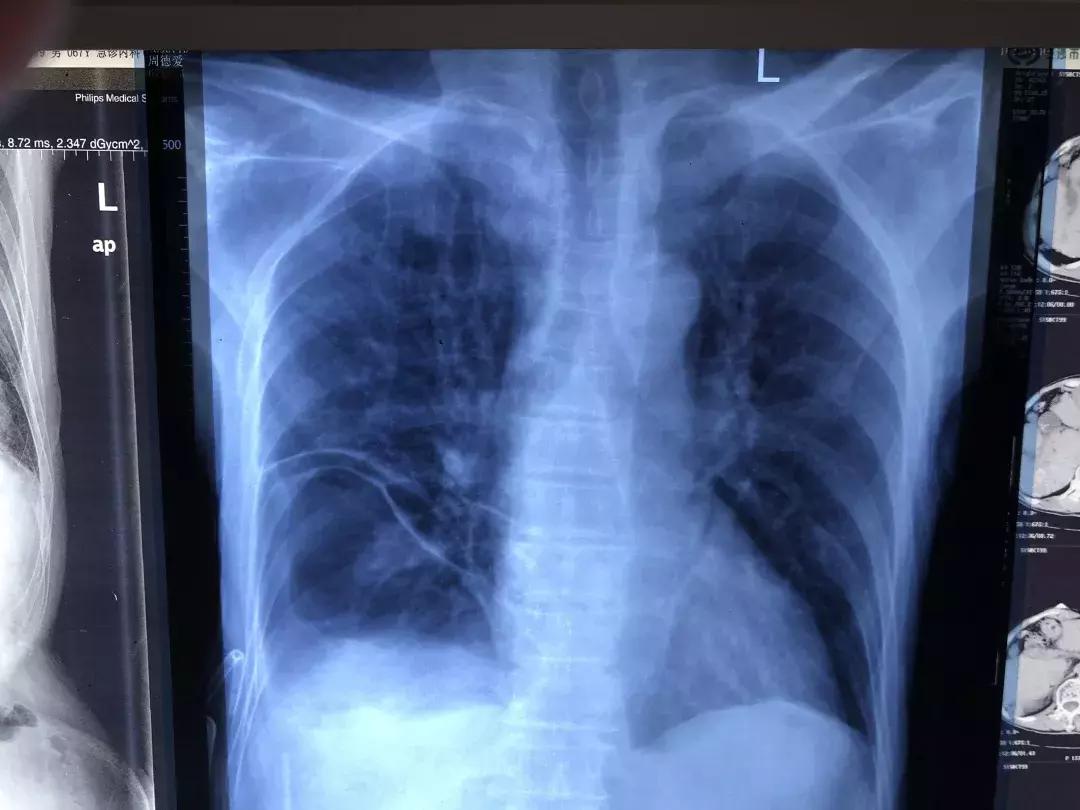

术后,移位至胸腔的腹腔脏器回归原位。

手术后胸腔无积液。